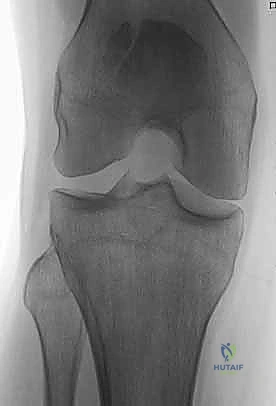

الأشعة السينية (X-rays): هي الخطوة الأولى والأساسية. يتم أخذ صور من زوايا متعددة:

- المنظر الأمامي الخلفي (AP View): لتقييم النمط العام للكسر.

- المنظر الجانبي (Lateral View): حاسم جداً لتقييم مدى تباعد أجزاء الكسر (Displacement) وعدم انتظام السطح المفصلي (Articular step-off).

- منظر السماء (Skyline View): مفيد لرؤية الكسور الطولية وتقييم التمفصل بين الرضفة وعظم الفخذ، ويتم إجراؤه إذا كانت حالة المريض تسمح بثني الركبة قليلاً.